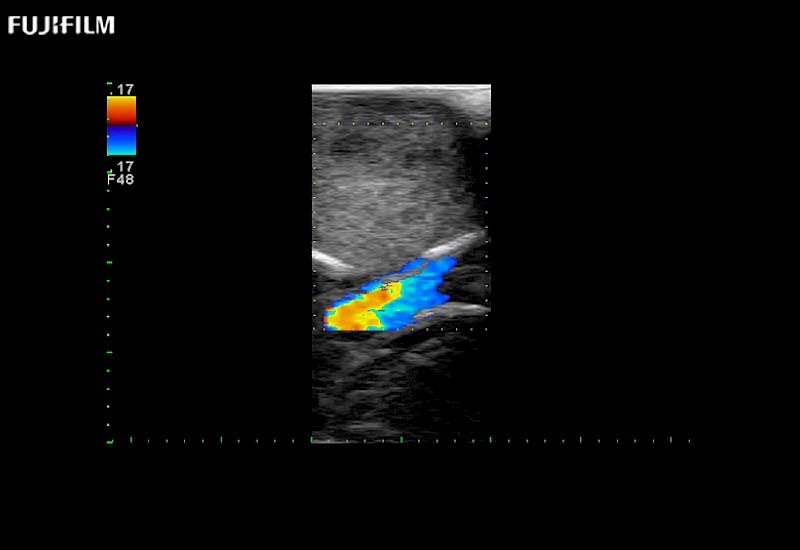

Extraordinary high-resolution digital imaging

Exceptional transducers

Multi-Parametric imaging modalities

Our dedication to neurosurgery allows us to offer superior image quality, outstanding system reliability and intuitive use of cutting edge technology.